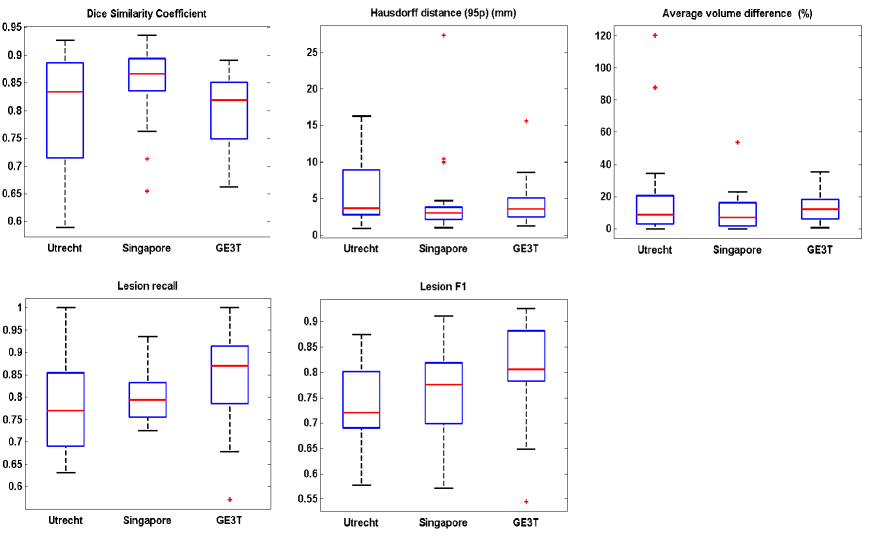

Figure 6 plotted the distributions of segmentation performances on scans from the three scanners, with each sub-figure showing performances using one of the five metrics. It could be observed that the segmentation performance on Utrecht was relatively poor. A few outliers (hard examples) were found in Utrecht which appeared to contain relatively more small lesions and blurred slices after checking the original slices and segmentation results. Section 5 presents a further analysis of these outliers, revealing the challenge of WMH segmentation task. In general, the averaged dice similarity coefficient, Hausdorff distance and lesion recall achieved by the proposed system on 60 cases were 87%, 3.6mm and 85%, respectively. This shows its effectiveness in aspects of overlapping, localization accuracy and overall lesion detection. Table S1 in the supplemental material reports extensive results allowing comparison on every case of the public training dataset.